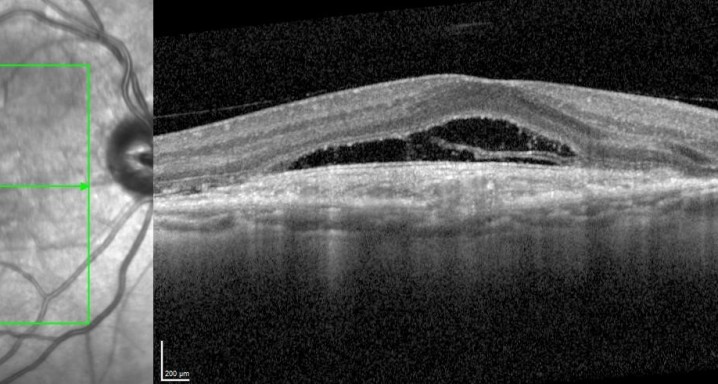

El estudio evaluará la eficacia, seguridad y farmacocinética de ranibizumab 100 mg/ml entregado a través de un dispositivo de liberación continuada (PDS) recargado cada 36 semanas en comparación con una recarga cada 24 semanas en pacientes con degeneración macular relacionada con la edad neovascular (nAMD).

Pacientes mayores de 50 años diagnosticados de DMAE neovascular en los 9 meses anteriores a la visita de selección.

DMAE seca o atrófica